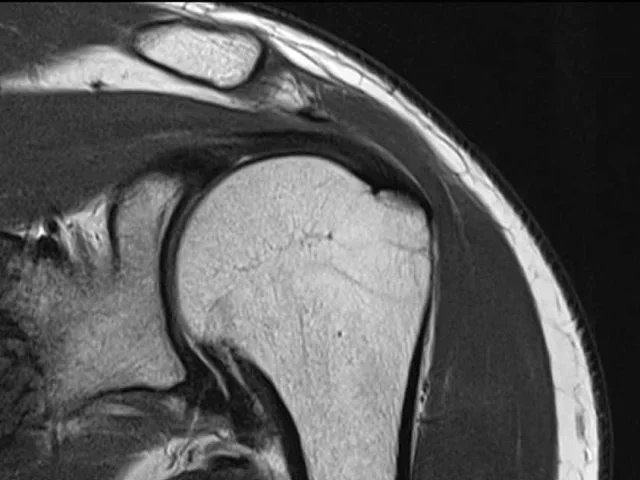

La resonancia magnética de hombro es una técnica de diagnóstico por imagen que permite obtener una visión detallada de la articulación del hombro y los tejidos que lo rodean. Este estudio es esencial para evaluar lesiones en tendones, músculos y tejidos circundantes, así como para el diagnóstico de diferentes padecimientos, la planificación de tratamientos y el monitoreo de enfermedades crónicas del hombro.